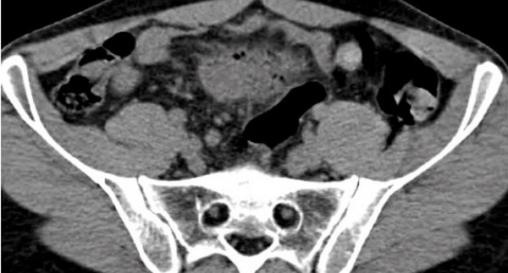

Rectocolite hémorragique

Aspect endoscopique de rectocolite hémorragique sans critère de gravité.